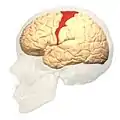

Brodmann area 4 (orange) | |

Brodmann area 4 refers to the primary motor cortex of the human brain. It is located in the posterior portion of the frontal lobe.

Brodmann area 4 is part of the precentral gyrus. The borders of this area are: the precentral sulcus in front (anteriorly), the medial longitudinal fissure at the top (medially), the central sulcus in back (posteriorly), and the lateral sulcus along the bottom (laterally).

Image

front view. Lateral view.

Lateral view. Medial view.

Medial view. Lateral surface.

Lateral surface.